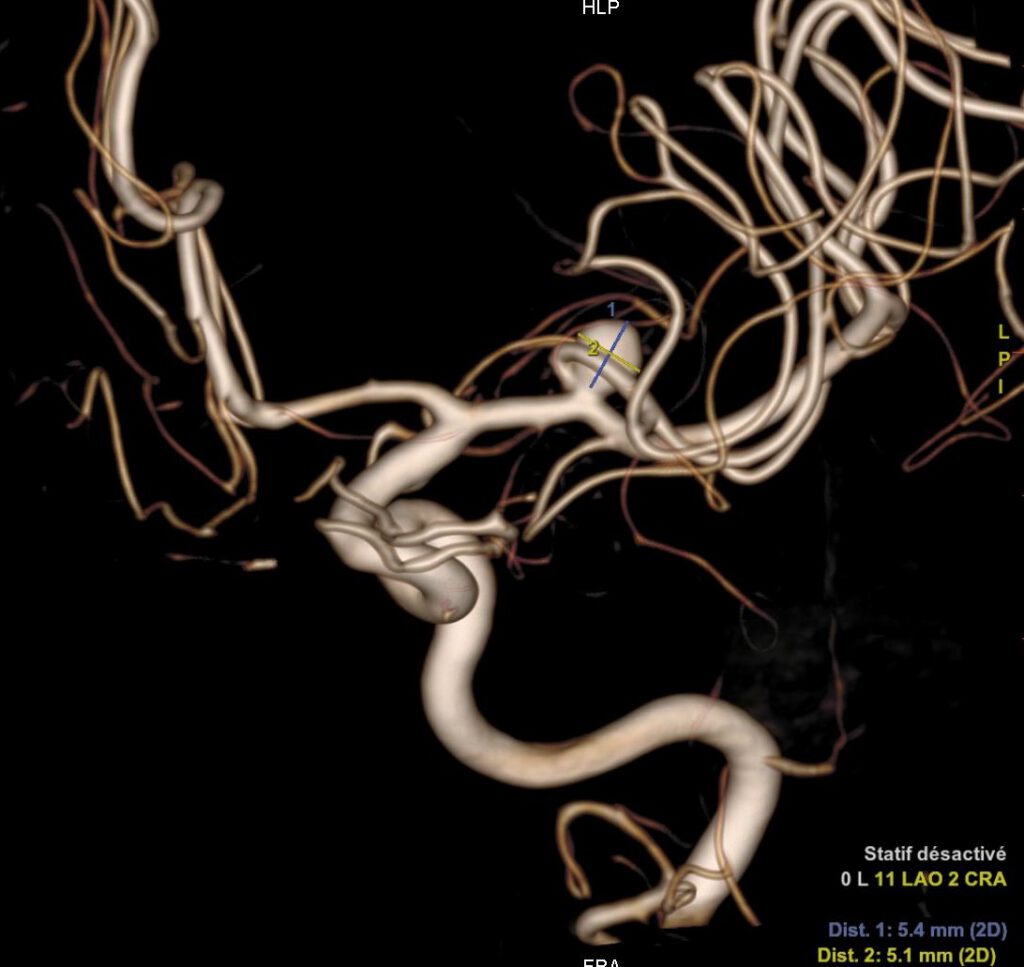

L’artériographie cérébrale, ou angiographie cérébrale, est une technique d’imagerie médicale diagnostique invasive qui permet de visualiser les vaisseaux sanguins du cerveau. Elle consiste à injecter un produit de contraste iodé directement dans les artères, via un cathéter (petit tuyau), ce qui rend les vaisseaux visibles par les systèmes d’imagerie à rayons X. Cette procédure est réalisée par un neuroradiologue interventionnel et permet d’obtenir des images très détaillées du réseau vasculaire cérébral.

L’artériographie cérébrale est utilisée pour diagnostiquer des pathologies vasculaires, tels que les anévrismes intracrâniens, les malformations ou fistules artério-veineuses, les vascularites et les sténoses artérielles. Il s’agit d’un acte interventionnel à visée diagnostique. L’extrême précision des images permet aux médecins de comprendre en détail et en 3D l’état vasculaire du patient et de décider des meilleures options de traitement.

L’artériographie cérébrale est la méthode la plus précise et l’examen de référence pour diagnostiquer les pathologies des vaisseaux sanguins du cerveau. Elle permet un diagnostic détaillé des affections vasculaires cérébrales, bien plus fin que d’autres techniques d’imagerie comme l’IRM ou le scanner. Grâce à sa haute résolution spatiale, elle est particulièrement efficace pour guider les traitements, comme l’embolisation d’un anévrisme.

Vous Avez un Anévrysme Intracrânien | Société Française de Neuroradiologie (sfnr.net)